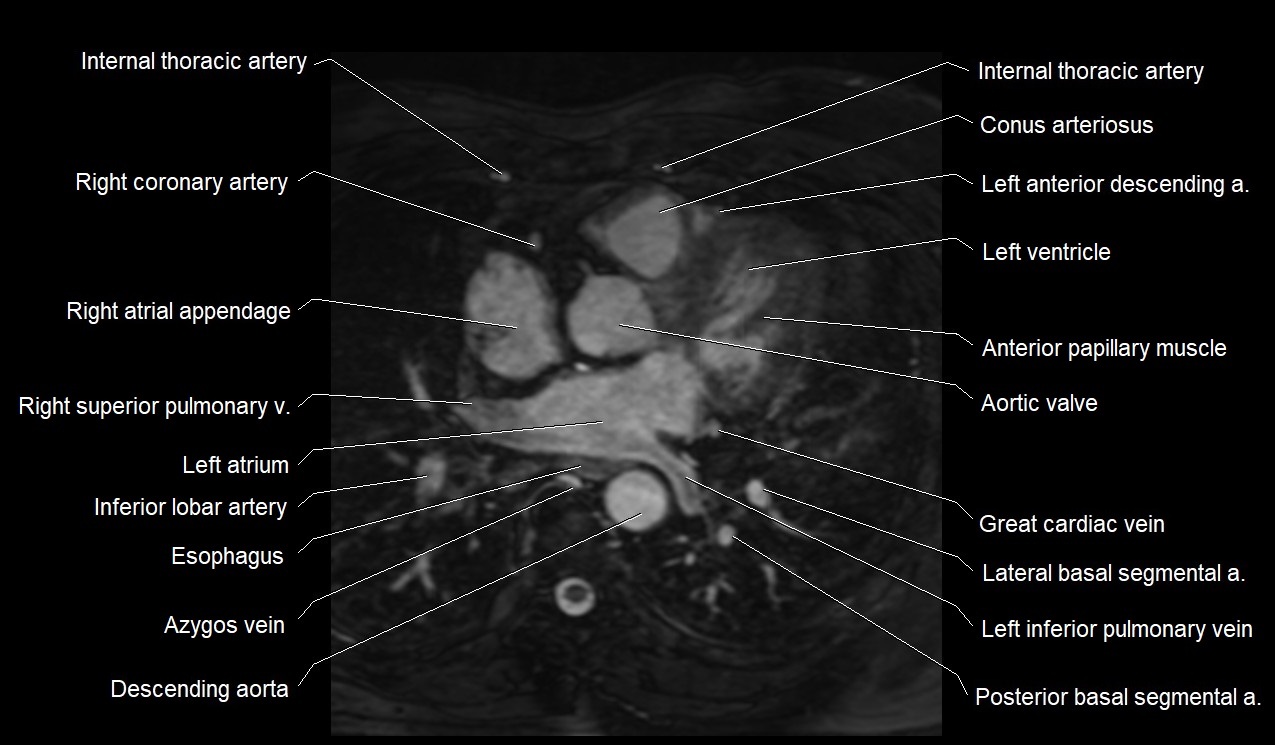

MRI image